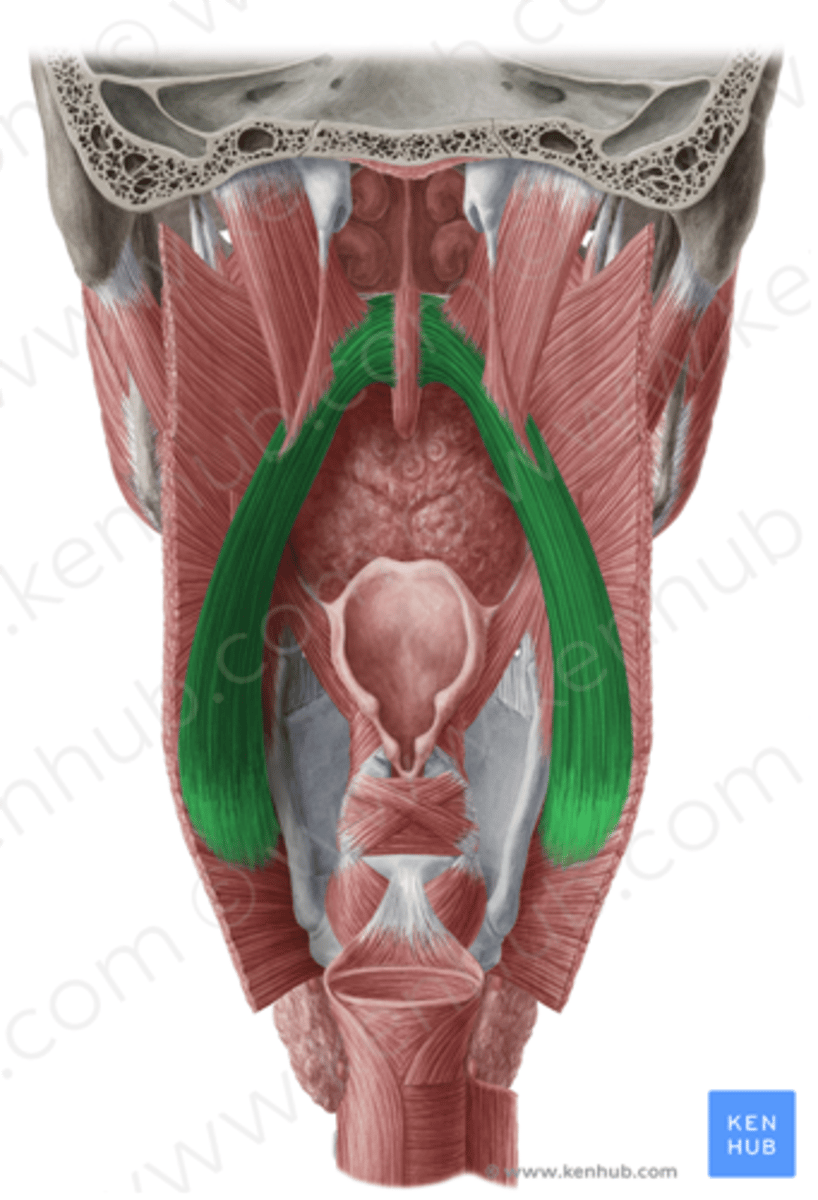

Superior Constrictor Figure

Middle Constrictor Figure

Thyropharyngeus Figure

Stylopharyngeus Figure

Salpingopharyngeus Figure

Palatopharyngeus Figure